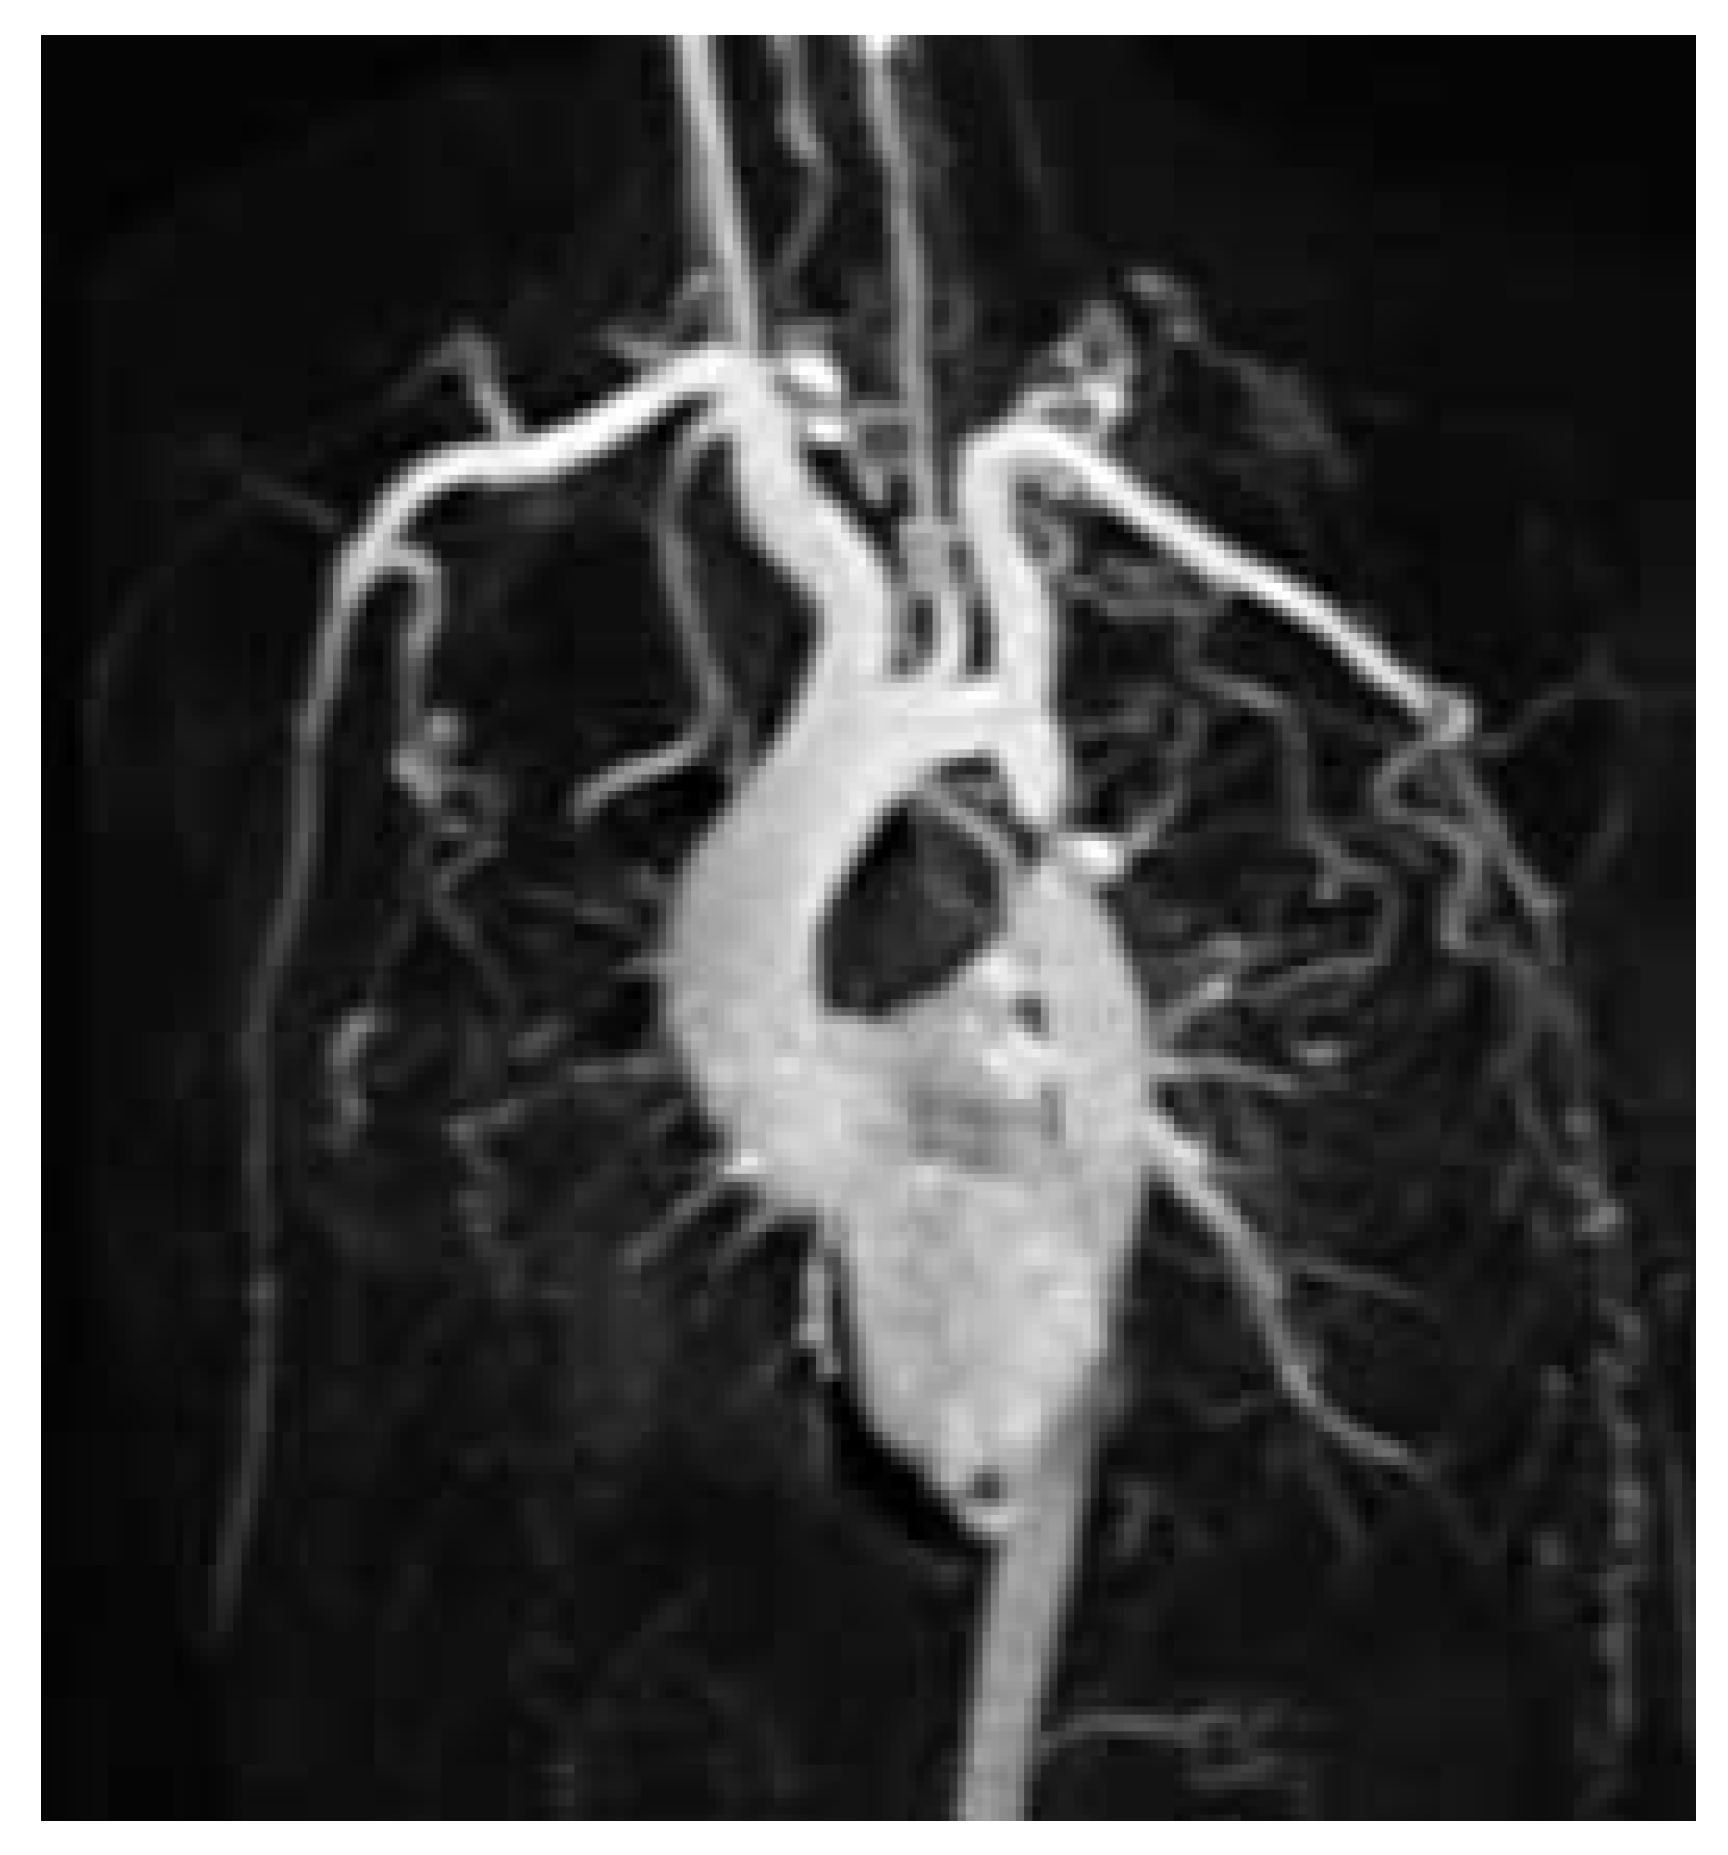

Figure 2. Severe postductal coarctation with poststenotic saccular aneurysm and extensive collateral formation (CMR 3D contrast enhanced acquisition).

A cardiovascular magnetic resonance study (CMR) was performed at our institution in order to assess the exact location, the degree and severity of the aortic stenosis and to rule out associated congenital anomalies. CMR showed a normal left ventricular mass (181 g, 95.3 g/m2, [normal: 91 ± 11 g/m2]), a moderately reduced left ventricular ejection fraction of 37.6%, a diffuse, apically pronounced hypokinesia with apical trabeculations (fig. 1), and no late contrast enhancement. In CMR, the aortic root was slightly dilatated (40 mm), the ascending aorta was normal but the aortic arch was slightly hypoplastic. The proximal part of the descending aorta showed a severe postductal stenosis (fig. 2) of 28 mm in length, a small poststenotic saccular aneurysm (confirmed by surgery, fig. 3), and an extensive collateral vascular system through the subclavian, scapular, internal thoracic, and intercostal arteries. The origin and proximal course of the coronary arteries as well as the pulmonary venous return were normal.

In summary, surgery is the preferred method in severe coarctation, especially when signs of aortic wall weakness, a postductal saccular aneurysm, and a dilatation of the aortic root are already present. Percutaneous dilatation is effective solely in mild coarctation and in recurrent coarctation following surgical repair. In severe coarctation percutaneous dilatation remains controversial because of the risk of incomplete relief of obstruction or aneurysm formation [3]. Furthermore, in subjects with a hypoplastic aortic arch associated with coarctation, as in our patient, percutaneous intervention is not a feasible approach [4].